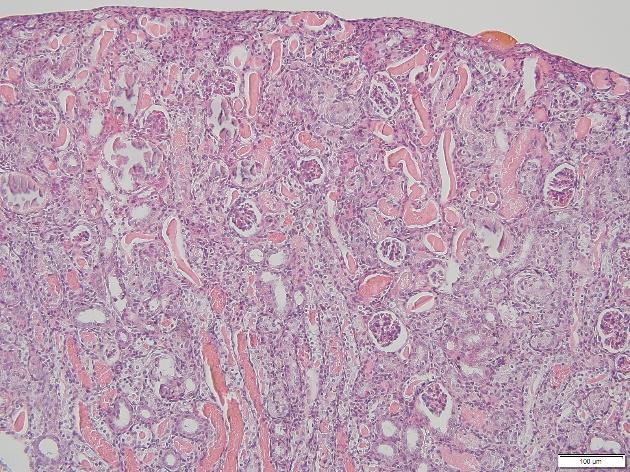

Images were taken on the microscope of the IRI kidneys I stained. Histological features such as protein casts and necrotic tubular cells can be seen which indicate injury due to induced IRI.